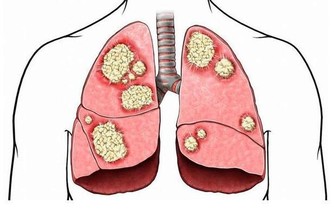

終於找到害她肩背疼痛的「元兇」——胰腺癌。

胰腺疾病不容易發現,如果能早點注意到發病信號,對治療很有幫助。

他介紹,現代人的飲食結構中,肉、蛋、奶和精細食物增多,蔬菜、粗糧減少,

再加上抽菸、喝酒、吃燒烤等不良習慣,導致胰腺疾病的發病率增多,且逐漸年輕化。

以前,胰腺癌患者基本都是五六十歲以上的人,而現在,30多歲的患者也時而可見。